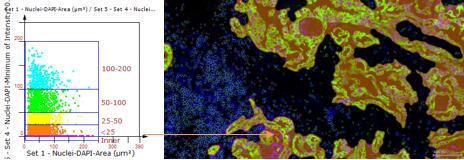

2、组织拆分、面积定量

例如下图:橙色-肿瘤区域

3、相关性分析:发现目标之间的内在关联